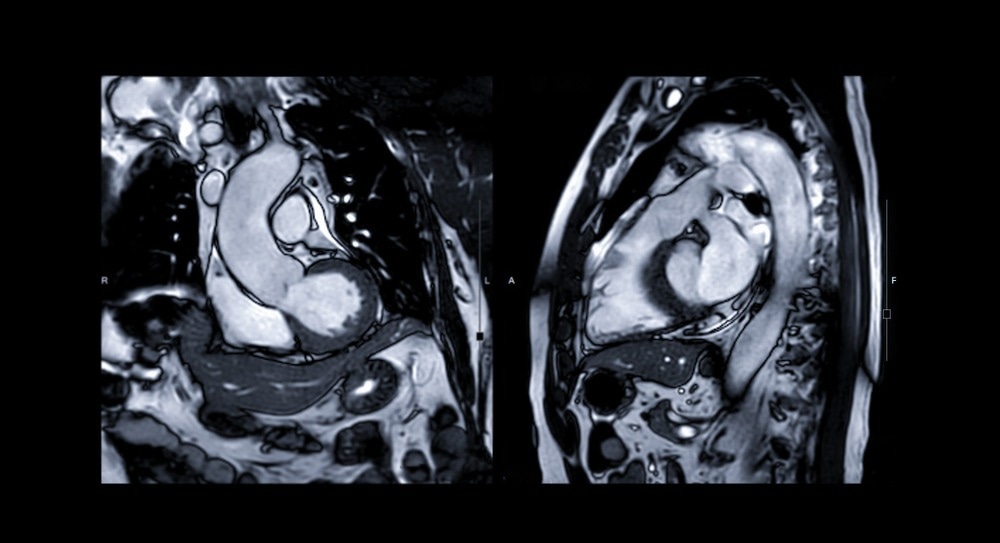

In recent years cardiovascular magnetic resonance imaging (MRI) has been recognized as a highly sensitive and specific tool for diagnosing myocarditis. This imaging technique has the unique potential to precisely visualize tissue changes, with the prospect of detecting characteristic changes in myocarditis – including interstitial and intracellular edema, hyperemia, capillary leakage, and (in more severe cases) cellular necrosis and ensuing fibrosis.

Contrast-enhanced MRI can also play a significant role in discriminating myocarditis from myocardial infarction, aiding in the evaluation of acute chest pain. In myocarditis, the infiltrates are usually located in the mid-wall and tend to spare subendocardial tissue, whereas the subendocardium is involved first in infarction. New contrast techniques using segmented inversion recovery gradient-echo pulse sequences and gadolinium enhancement can distinguish between diseased and normal myocardium even better.

Image Credit: Radiological imaging/Shutterstock.com